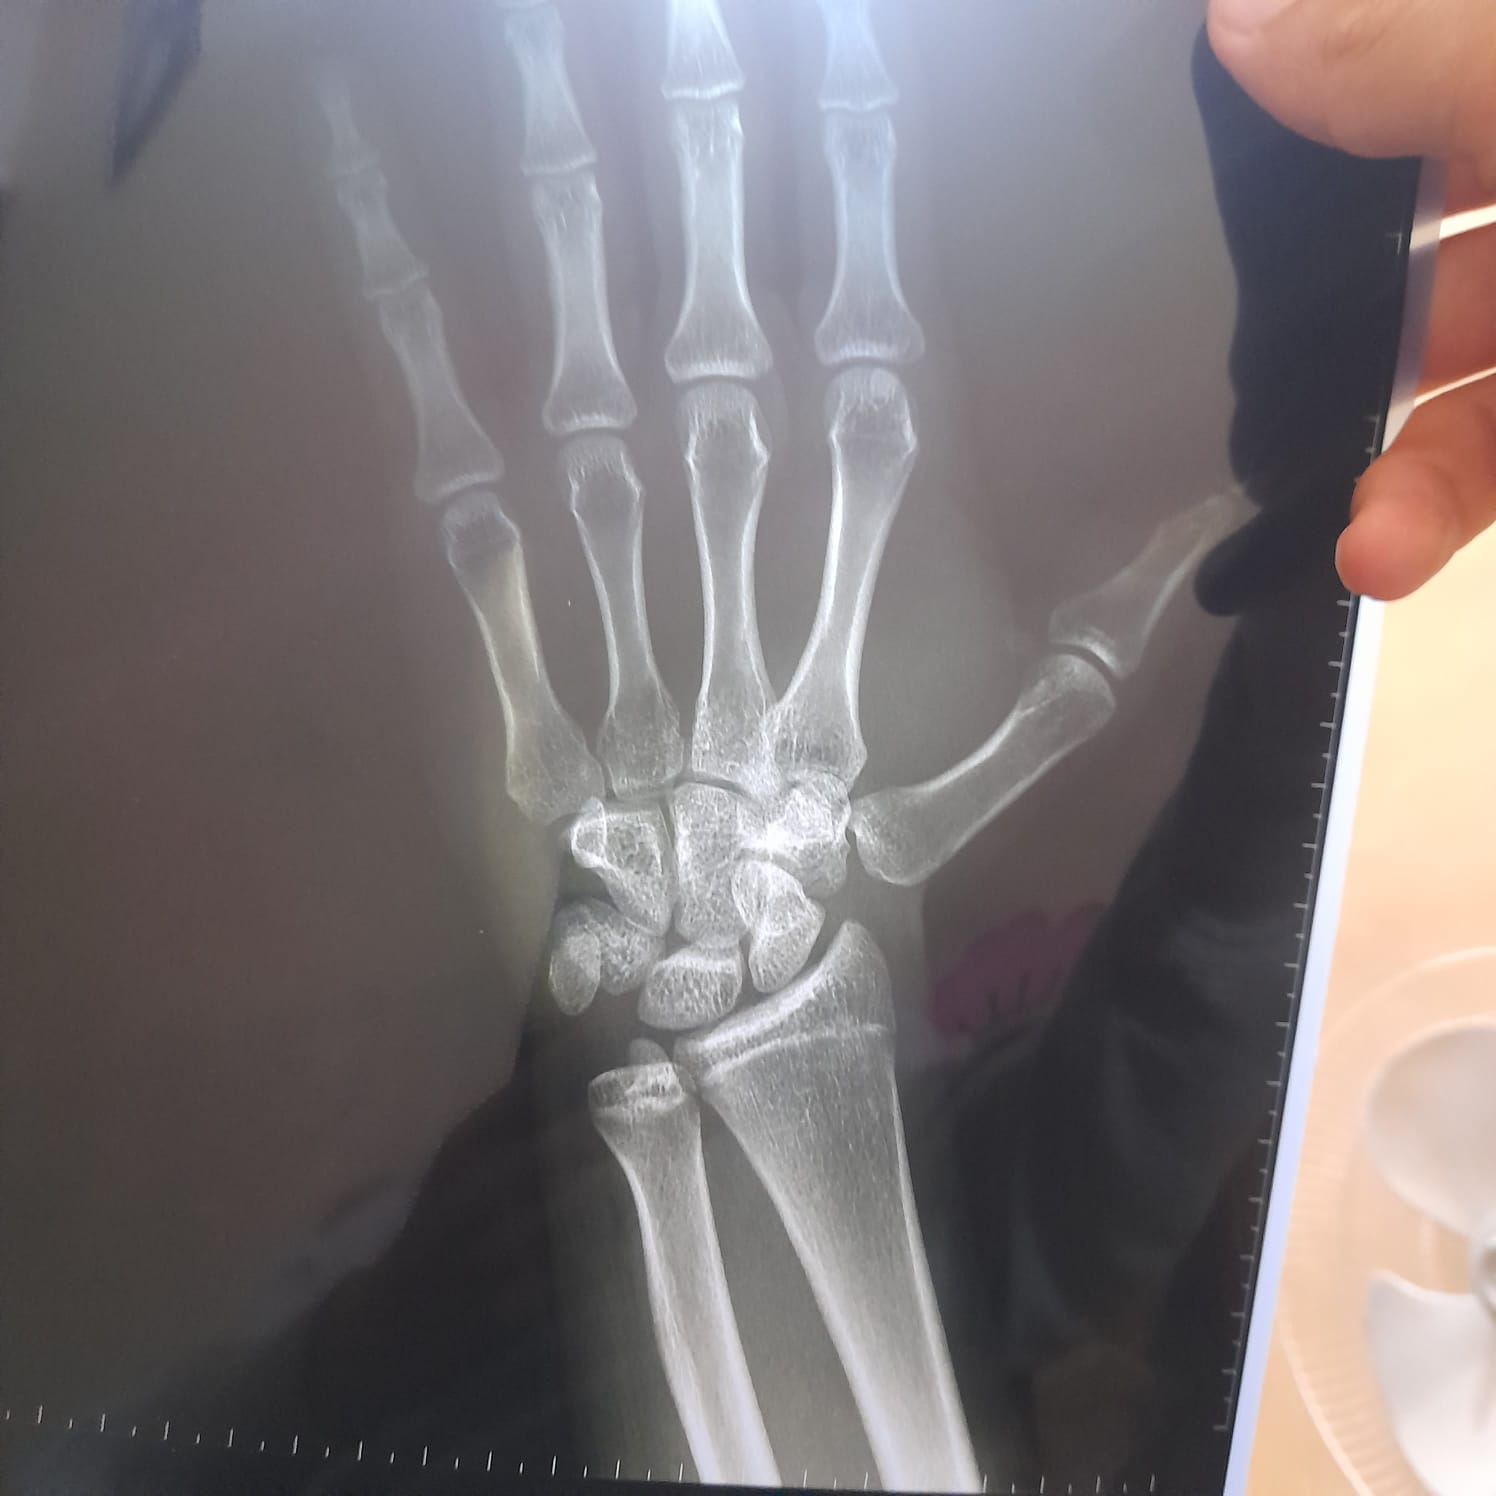

انا عمري 15 و 9 اشهر اريد ان اعرف اذا صفائح النمو مغلقة او مفتوحة

صفائح النمو ما زالت مفتوحة وليست مغلقة بالكامل بفضل مراجعة طبيب الغدد الصماء 0 2025-11-18T11:03:29+00:00 2025-11-18T11:03:29+00:00

صفائح النمو ما زالت مفتوحة وليست مغلقة بالكامل بفضل مراجعة طبيب الغدد الصماء